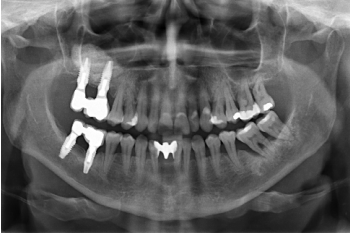

Una vez transcurridos seis meses desde la inserción de los implantes extra-cortos, se procede a la colocación de la prótesis definitiva, en este caso, atornillada y con un componente intermedio (transepitelial), al igual que se confecciona del mismo modo la prótesis inferior del tercer cuadrante. En este punto cronológico, la filosofía de

trabajo mediante prótesis atornillada con transepitelial y la búsqueda de hermetismo y ajuste pasivo es la filosofía dominante para la rehabilitación sobre implantes y continúa siéndolo hoy en día (Figura 12).

Finalmente, podemos observar la estabilidad de ambos tratamientos en la radiografía final a los 8 años, donde ambos se mantienen estables sin pérdidas óseas (Figura 13)